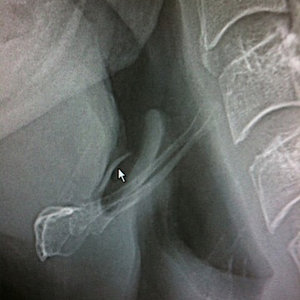

Jeśli nie udało nam się wyjąć ości w warunkach domowych, konieczna jest wizyta u laryngologa lub odwiedzenie najbliższej stacji pogotowia. Lekarz dysponuje odpowiednimi narzędziami i technikami (może użyć wziernika, a nawet specjalnej kamery, by dostrzec ość, która utkwiła gdzieś głęboko). Nie powinno się zaniedbywać sprawy, gdyż na ogół wbita ość sama nie wyjdzie, a może spowodować stan zapalny i niebezpieczne powikłania, na przykład sepsę.